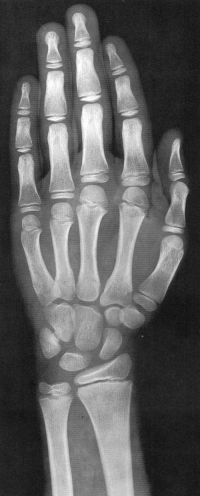

Sexo Masculino

17 anos